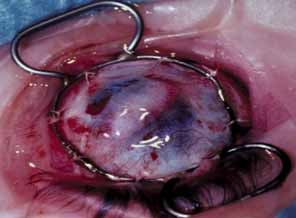

Both autosomal-dominant and autosomal-recessive forms of CHED have been distinguished, and distinct genetic loci for each form have been found on chromosome 20.141,142 CHED clinically presents with bilaterally symmetric, full-thickness stromal edema increasing the corneal thickness two- to three-times its normal size (Fig. 25). In addition, there is diffuse, nonbullous epithelial edema without evidence of inflammation or vascularization of the cornea. The corneal edema may be nonprogressive or it may worsen with time.143 The only treatment for severe edema and visual loss is penetrating keratoplasty, which carries a fair prognosis.144

Fig. 25 Congenital hereditary endothelial dystrophy. A. Histopathology demonstrates diffuse corneal edema with fluid pockets separating stromal collagen fibrils distorting stromal lamellae. B. Slit views show corneal stroma to be two- to three-times normal thickness.

Histopathological features include distorted stromal lamellae with large-diameter collagen fibrils and fluid pockets separating stromal collagen fibrils. Descemet's membrane is thinned with a normal anterior 110-nm banded zone and a variably thickened posterior nonbanded zone consisting of disorganized collagen.145